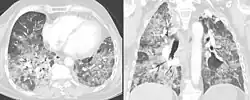

Pneumonite de hipersensibilidade ou alveolite alérgica extrínseca é uma doença pulmonar caracterizada pela inflamação e dos alvéolos pulmonares por uma reação alérgica (hipersensibilidade tipo 4) à inalação de poeira ou vapor com proteínas orgânicas por vários anos. Acometidos são normalmente expostos ao alérgeno devido a sua profissão ou moradia e podem ser obrigados a mudar de carreira ou casa para recuperar-se. O uso de máscara é recomendado para prevenir os episódios de pneumonite.

O diagnóstico é baseado na história de sintomas após a exposição ao alérgeno e em testes clínicos. Exames de sangue indicam sinais de inflamação pouco específicos, a radiografia de tórax revela áreas de opacidade difusa, pode haver edema e fibrose, e testes de função pulmonar revelam doença pulmonar restritiva.[6]